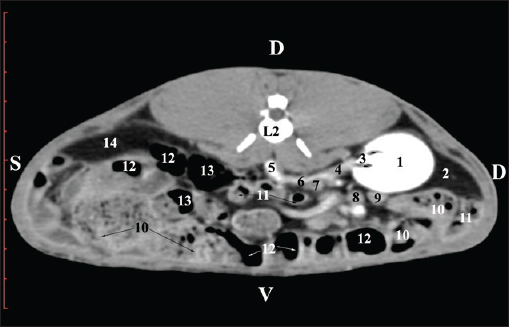

At the L2 level, the right kidney was in contact with the liver’s proc. caudatus, pars descendens of the duodenum, and the ileum. Pelvis renalis was a distinct hypoattenuated funnel-shaped soft tissue finding, whose narrow end pointed at the renal hilum and passed into the ureter. Recessus renalis was a clearly visible hypoattenuated widening of the central part of the renal pelvis in the dorsal and ventral directions (Figs. 4 and 5).

Fig. 4. Pre-contrast CT anatomical scan of the regio-abdominis media at the cranial L2 edge level. (1) Ren dexter; (2) pelvis renalis; (3) lobus caudatus (proc. caudatus) with visceral adipose tissue; (4) pars descendens of the duodenum; (5) ileum; (6) jejunum; (7) colon ascendens; (8) cecum; (9) colon transversum; (10) colon descendens; (11) lien; (12) pars transversa of the duodenum ; (*) ureter; (white arrow) recessus renalis.

Fig. 5. Pre-contrast computed tomography (CT) anatomical scan of the regio-abdominis media at the caudal L2 edge level. (1) Ren dexter; (2) pelvis renalis; (3) lobus caudatus (proc. caudatus) with visceral adipose tissue; (4) gl. adrenalis dextra; (5) ileum; (6) jejunum; (7) colon ascendens; (8) cecum; (9) colon transversum; (10) colon descendens; (11) lien; (*) ureter; (white arrow) recessus renalis.